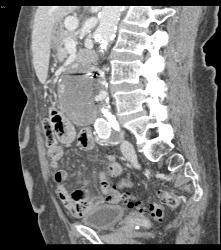

CTA of Iliacs With Auto-bone Removal